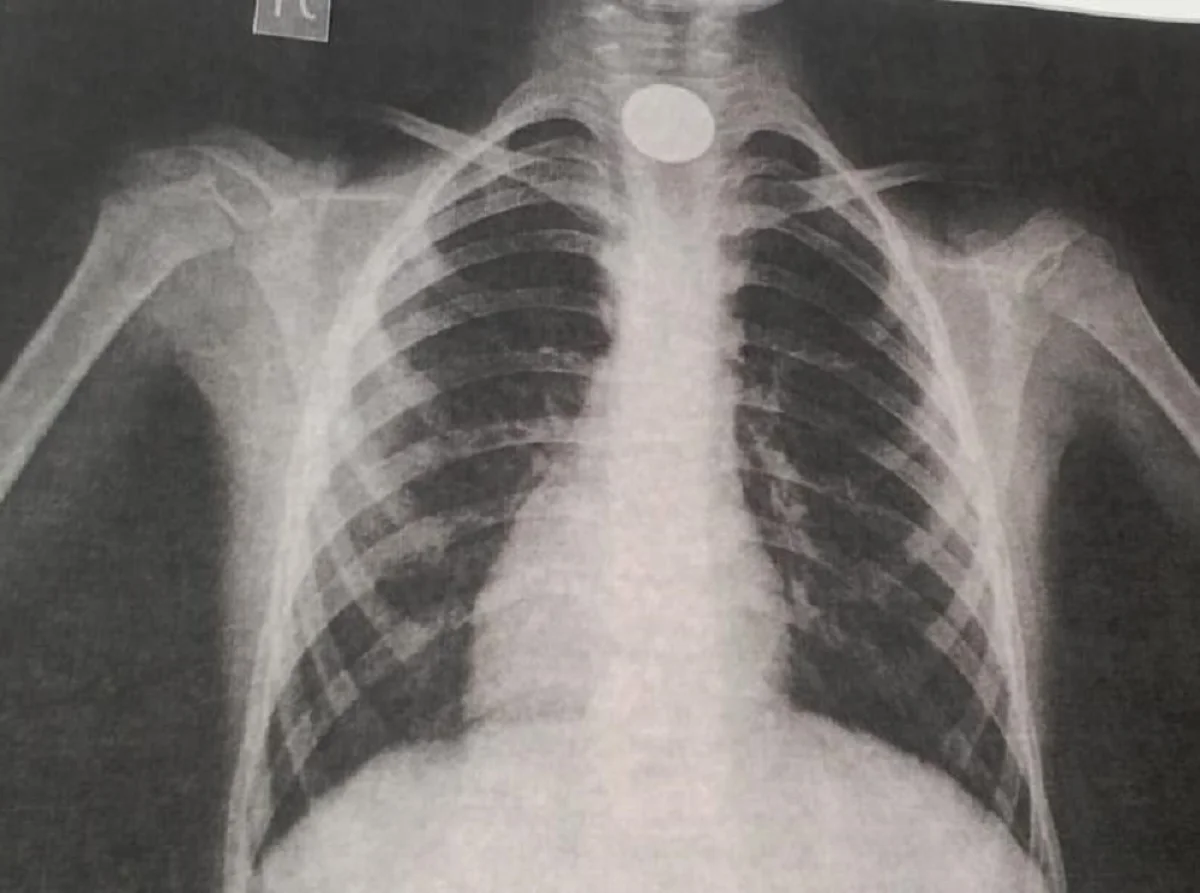

Пятилетний ребенок с инородным телом в пищеводе, которое вызвало затрудненное дыхание, поступил в клинику 22 сентября. Врач-эндоскопист Роллан Елеусинов совместно с бригадой эндоскопистов и анестезиологов клиники провели операцию по изъятию монеты номиналом 100 тенге из желудка маленького пациента.

- Монета находилась в пищеводе ребенка. Когда приступили к операции, она уже опустилась в желудок. Операция длилась около 40 минут. Сейчас ребенок чувствует себя удовлетворительно и идет на поправку. Просим родителей быть более внимательными к маленьким детям. Убирайте с поля зрения мелкие предметы: магнитики, копейки, иголки, булавки, батарейки и т.п. Подобные ситуации случаются довольно часто. Благодаря оперативному реагированию и вмешательству положительный исход ситуации очевиден, – отметили в медицинском учреждении.